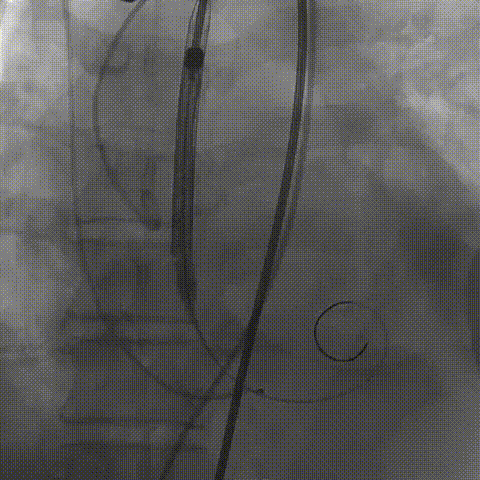

瓣膜(AV29)工作位正交体位造影位置良好,左冠显影正常

瓣膜(AV29)完全脱钩释放后23mm球囊充分后扩,冠脉灌注良好

最后造影

术后血流动力学

瓣膜工作状态良好,极微量瓣周漏,血流动力学有效改善